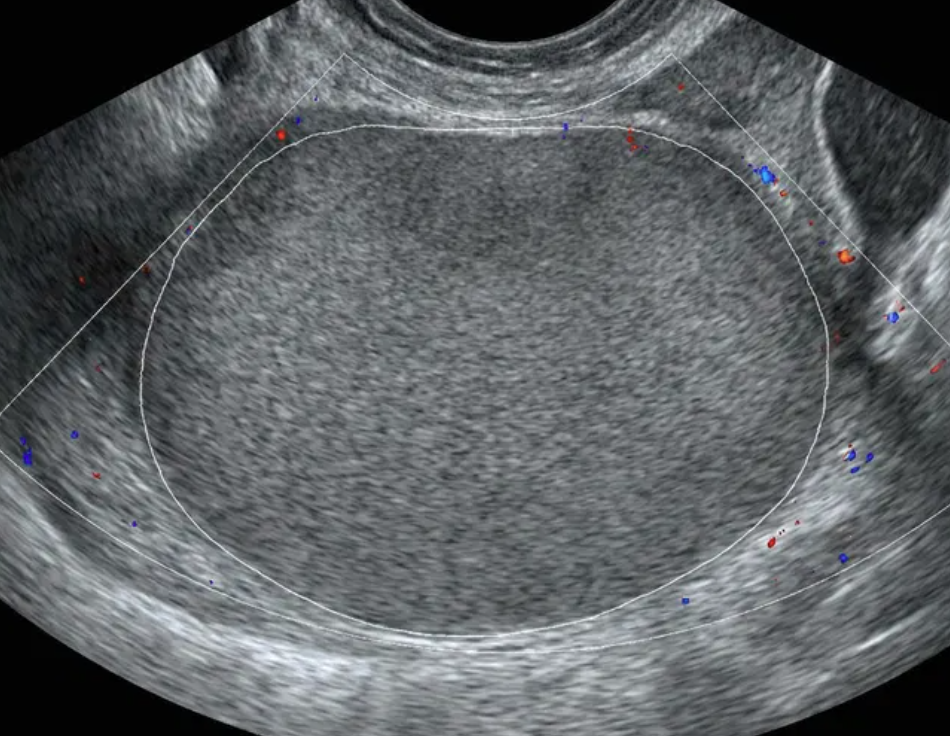

Risco: 10-<50%Cisto multilocular sem componente sólido ≥ 10 cm ou com IC = 4, cisto unilocular/multilocular com componente sólido, lesão sólida com superfície lisa e IC = 2–3.

Cisto multilocular, sem componente sólido

Cisto unilocular com componente sólido

Cisto multilocular com componente sólido

Lesão sólida

Conduta

Opções de imagem incluem US com especialista (se disponível) e RM (com O-RADS MRI score), de acordo com o protocolo do ginecologista-oncologista. Atendimento pelo ginecologista com consulta ao ginecologista-oncologista ou exclusivamente pelo ginecologista-oncologista.